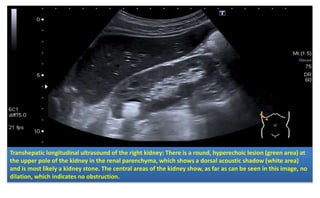

• Best initial in pregnancy : abdominal US

– Can detect hydronephrosis

– Can be used if the CT unavailable

False-negative results are common in early obstruction.

Transhepatic longitudinal ultrasound of the right kidney: There is a round, hyperechoic lesion (green area) at

the upper pole of the kidney in the renal parenchyma, which shows a dorsal acoustic shadow (white area)

and is most likely a kidney stone. The central areas of the kidney show, as far as can be seen in this image, no

dilation, which indicates no obstruction.